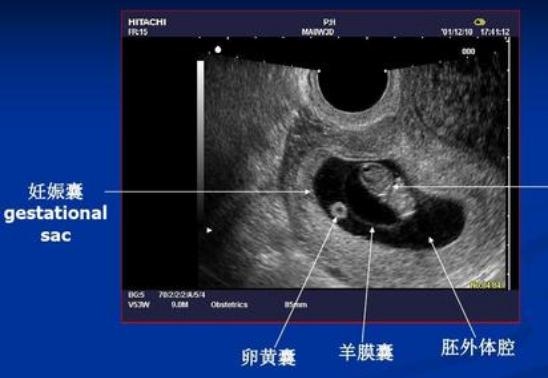

比如在 怀孕早期,根据孕囊的大小、胎芽的长度来判断怀孕多少周了。